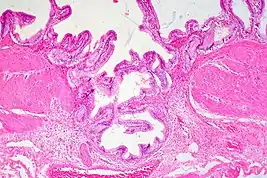

Ultrasound is the preferred initial diagnostic choice for suspected gallbladder disease. Several distinct features of adenomyomatosis are discernable using ultrasound, making it a reliable modality for diagnosis.[4][5][6] The most characteristic features seen on ultrasound are the Rokitansky-Aschoff sinuses, which present either as echogenic foci when filled with biliary sludge/gallstones or anechogenic foci when filled with normal bile.[4][5][6] Other key features that may be seen include wall thickening and ring-down artifacts known as "comet tails" (produced by reverberations of sound between the sinuses).[4][5][6] Ultrasound can also distinguish between diffuse, segmental, and localized variants of adenomyomatosis based on morphology.[5][6]

In some cases, gallbladder wall thickening may be seen on ultrasound but is poorly defined and lacking specificity, particularly if the characteristic Rokitansky-Aschoff sinuses are not visualized. This can make it difficult to distinguish adenomyomatosis from other conditions that result in gallbladder wall thickening such as gallbladder cancer.[4][5][6] In these cases, MRI can prove helpful in providing the resolution needed for diagnosis. Especially effective is the T2-weighted MRI at visualizing the pathognomonic Rokitansky-Aschoff sinuses, which appear as round-shaped hyperintense cystic spaces that align in a curvilinear fashion along the gallbladder wall in a pattern described as the ”pearl necklace sign”.[4][5][6]